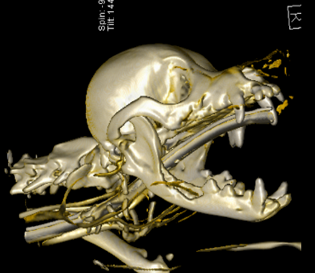

구강 종양